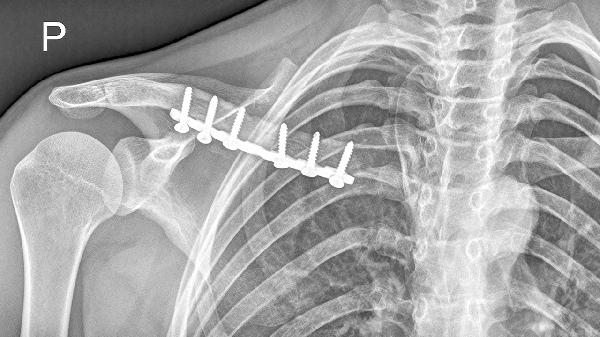

锁骨骨折错位严重时是否适合保守治疗需根据错位程度和并发症风险综合评估,主要考虑因素包括骨折端移位距离、是否合并血管神经损伤、患者年龄及功能需求。保守治疗适用于移位小于锁骨宽度1.5倍、无重要结构压迫的闭合性骨折,常用方法有八字绷带固定、锁骨带制动及康复训练。

骨折端横向移位超过锁骨宽度1.5倍或成角大于30度时,保守治疗易导致畸形愈合。此时骨折断端接触面积不足,局部血运破坏严重,骨痂形成缓慢,可能遗留肩关节功能障碍。儿童青枝骨折或老年人低需求活动者,可适当放宽指征。

运动员或体力劳动者建议手术优先。严重错位保守治疗可能遗留肩关节短缩畸形,影响上肢推举、负重功能。解剖复位可最大限度恢复锁骨长度和旋转角度,缩短康复周期。